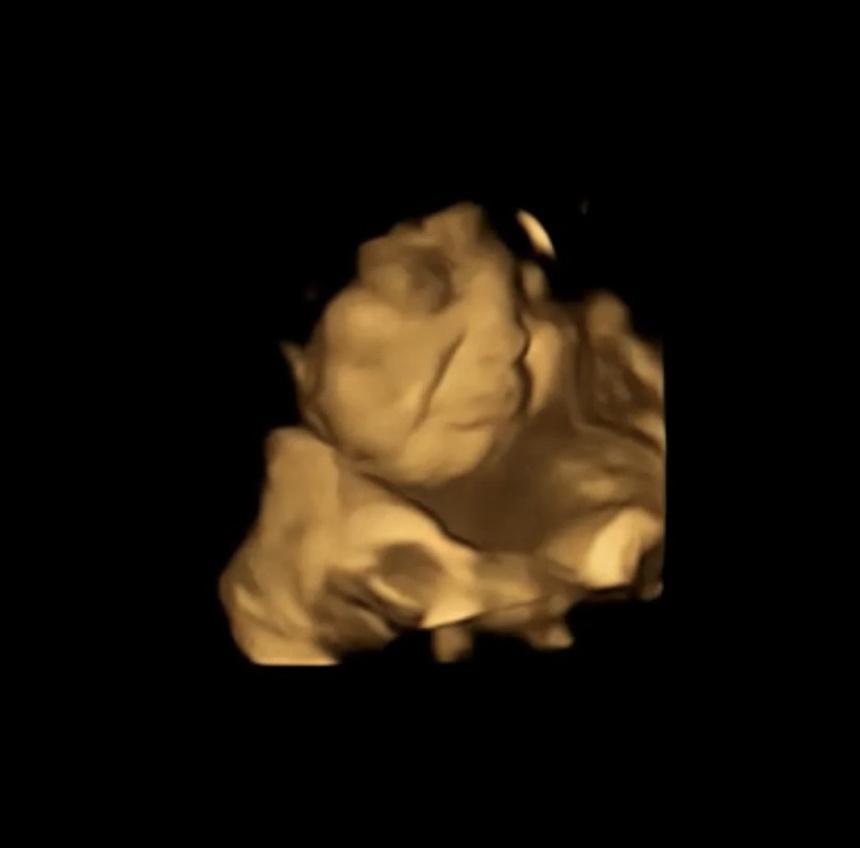

20 phút sau, kết quả siêu âm cho thấy hầu hết thai nhi tiếp xúc với hương vị cải xoăn có vẻ nhăn nhó, trong khi hầu hết thai nhi tiếp xúc với cà rốt dường như đang cười.

Trong khi đó, nhóm đối chứng (nhóm không nhận được những thay đổi gì mới khi tham gia thí nghiệm) không có những phản hồi giống nhau.

Các thai nhi trong nghiên cứu mới đây có tuổi thai 32 đến 36 tuần. (Thời gian mang thai trung bình kéo dài 40 tuần kể từ kỳ kinh cuối cùng).

Bà Reissland cho biết hình ảnh siêu âm cho thấy những phản ứng tương tự như phản ứng của trẻ em hoặc người lớn khi nếm thứ gì đó có vị đắng, nhưng vẫn chưa biết liệu bào thai có thực sự trải qua cảm xúc hay không thích theo cách tương tự hay không.

Bà Reissland nói: "Những cái nhăn mặt trong siêu âm có thể chỉ là những chuyển động của cơ đang phản ứng với một hương vị đắng".